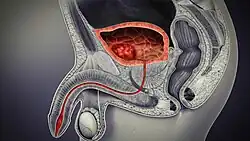

In humans, the bladder is a hollow muscular organ situated at the base of the pelvis. In gross anatomy, the bladder can be divided into a broad fundus (base), a body, an apex, and a neck.[5] The apex (also called the vertex) is directed forward toward the upper part of the pubic symphysis, and from there the median umbilical ligament continues upward on the back of the anterior abdominal wall to the umbilicus. The peritoneum is carried by it from the apex on to the abdominal wall to form the middle umbilical fold. The neck of the bladder is the area at the base of the trigone that surrounds the internal urethral orifice that leads to the urethra.[5] In males, the neck of the urinary bladder is next to the prostate gland.

In males, the prostate gland lies outside the opening for the urethra. The middle lobe of the prostate causes an elevation in the mucous membrane behind the internal urethral orifice called the uvula of urinary bladder. The uvula can enlarge when the prostate becomes enlarged.

The bladder is located below the peritoneal cavity near the pelvic floor and behind the pubic symphysis. In males, it lies in front of the rectum, separated by the rectovesical pouch, and is supported by fibres of the levator ani and of the prostate gland. In females, it lies in front of the uterus, separated by the vesicouterine pouch, and is supported by the elevator ani and the upper part of the vagina.[10]